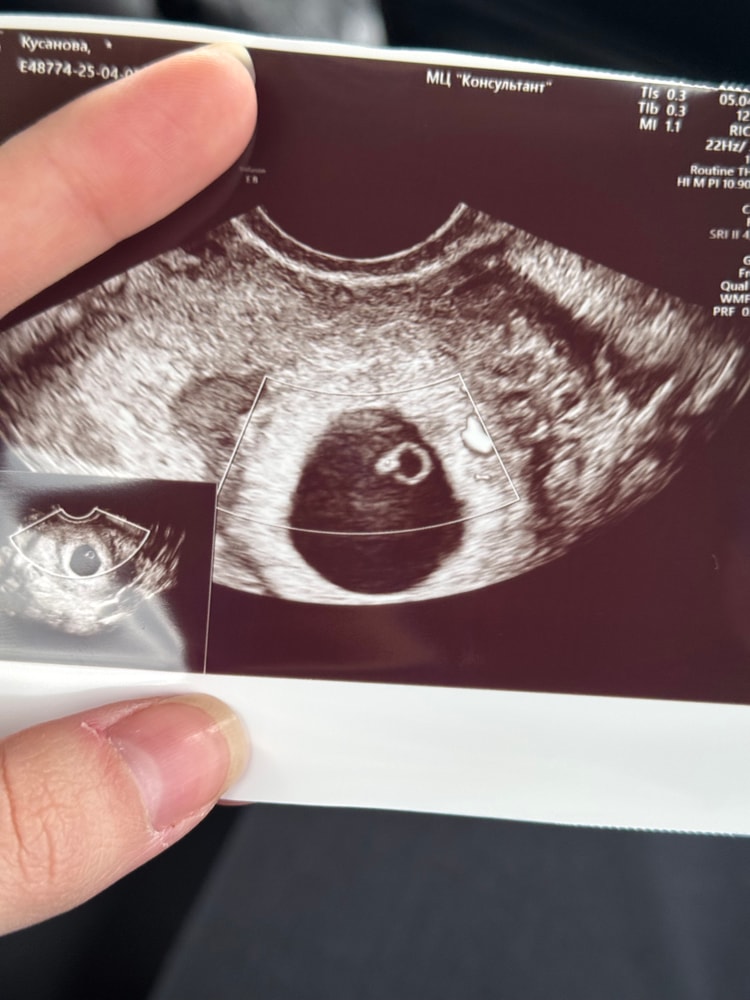

Второе УЗИ.

УЗИ, КТГ, доплер3 дня назад делала УЗИ, не повезло с врачом, сказала, что эмбриона нет и ПЯ не соответствует сроку по М, максимум 3-4 недели, либо не развивается.

Была эти дни на иголках, сегодня пошла к другому врачу, увидела эмбрион и пульсацию 😍

Очень успокоила меня, вот мое «кольцо с бриллиантом». 😍😁